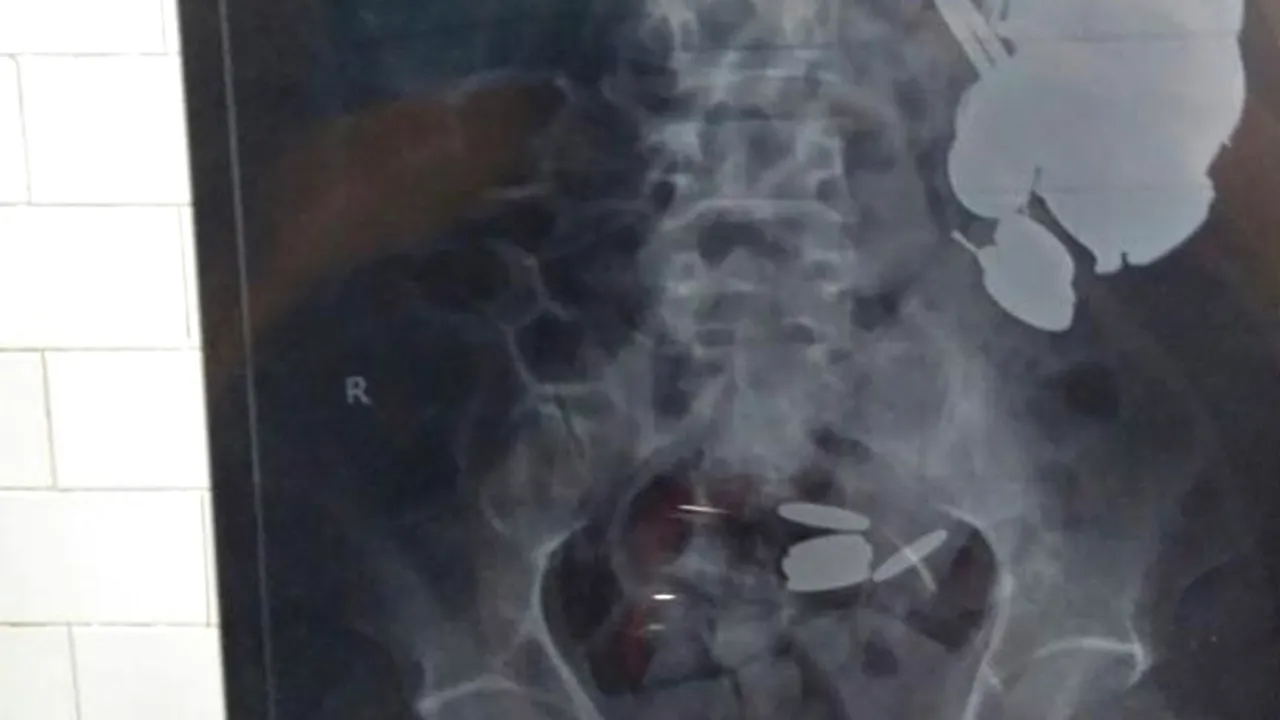

Un bărbat care a mers la doctor în India, acuzând dureri abdominale, iar doctorii au descoperit că are aproape cinci kilograme de obiecte metalice în stomac.

Radiografiile au arătat însă că omul are numeroase obiecte metalice în stomac, de la monede până la lame de ras.

Khan a fost operat în data de 24 noiembrie pentru îndepărtarea obiectelor. Medicii au extras 263 monede și 100 cuie din stomacul acestuia, în timpul unei operații de trei ore.